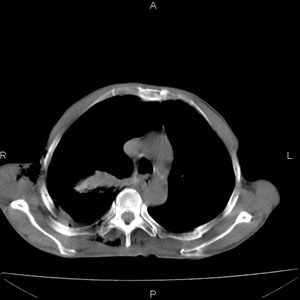

患者男,77岁,于3日前从树上摔下,头部查ct示蛛血,硬膜下出血,上腹部ct未见明显异常,右侧胸腔积液,左侧如常。肺部拍片示右侧肋骨多发骨折住院后今日来查肺部ct,我看到的是1。右侧胸腔血气胸并右肺上叶,中叶压缩性肺不张,2。右肺下叶肺挫伤并多发肋骨骨折,肌内及皮下积气3。左侧少量胸腔积液,我想请教的是3天前左侧胸腔里没有积液今天怎么出现了呢,是什么原因呢?请讨论。

考虑外伤性迟发性胸腔积液。

本人考虑有两种可能1)外伤迟发性的改变。

2)当时肋骨没有刺破肋间血管,可能这3天中由于运动导致